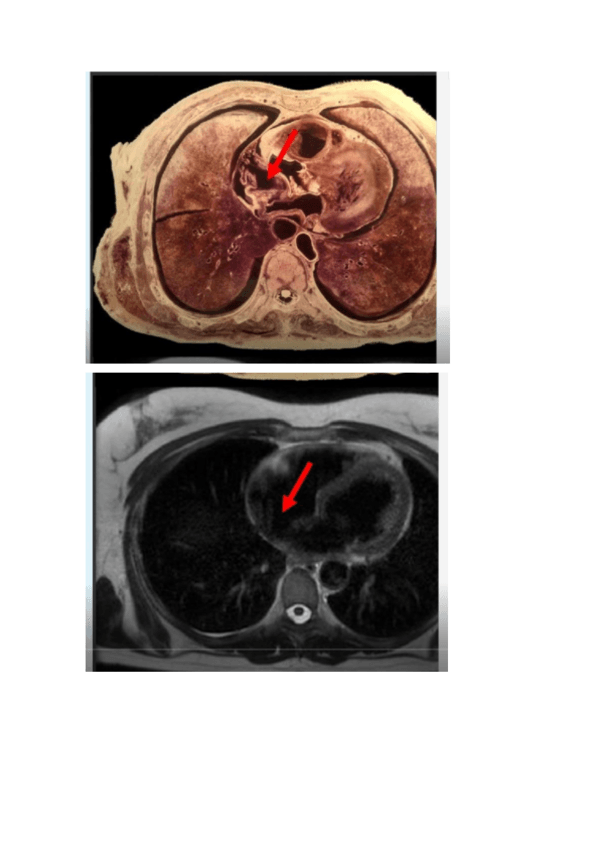

Imagenes-de-Torax-con-nombres.pdf

Practicas-12-y-13-resueltas-con-nombres.pdf

Imagenes-de-Torax-con-nombres-2.pdf